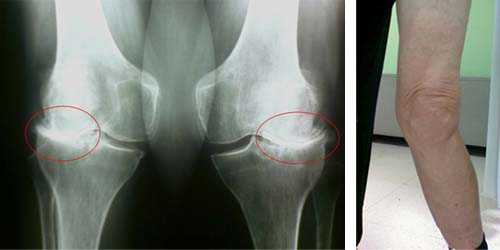

Для обоих заболеваний, в первую очередь, необходимо сдать не только анализ крови, обязательно рентгеновский снимок сустава. При артрозе происходит сужение щели между суставами, остеофиты (костные разрастания), деформации и остеопороз. Возможно назначение КТ, МРТ для уточнения изменений мягких тканей и костных структур.

Для артроза также характерно сужение щели и околосуставной остеопороз, однако они возникают на ранних стадиях (тогда, как при дегенерации, такие изменения начинаются только на 3 и 4 стадии). Если процесс имеет инфекционный характер часто формируются секвестры — участки некроза, окруженные здоровой тканью. При хроническом течение наблюдают вывихи, подвывихи шарнирных структур.